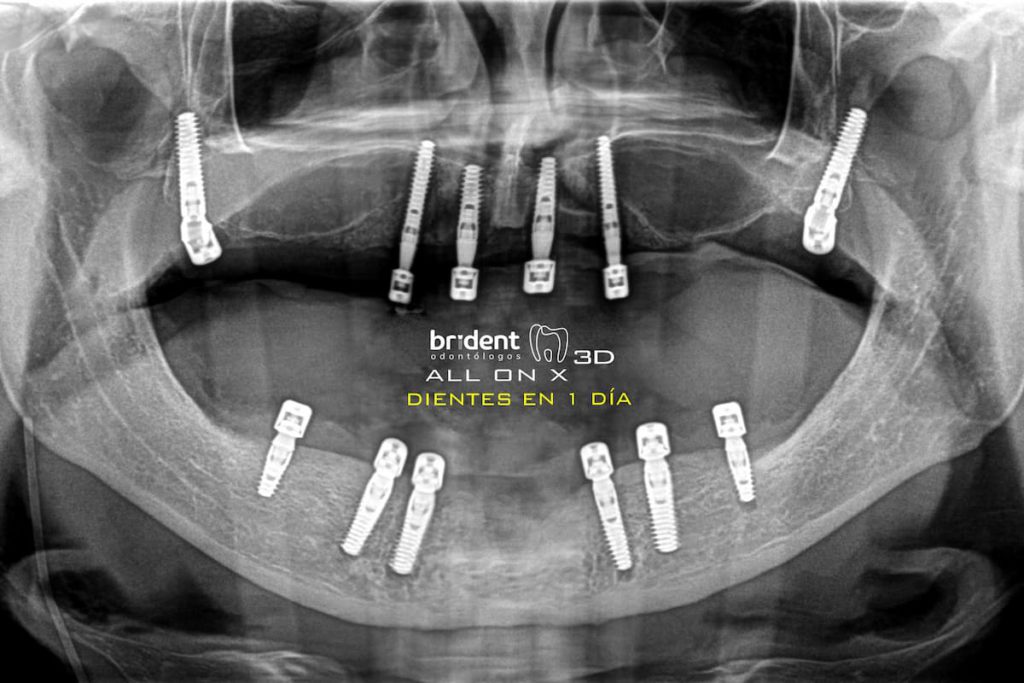

ALL ON X : Implantes en maxilar superior + dientes en 1 día

ALL ON X : Implantes en maxilar superior e inferior + dientes en 1 día.

Nuestro especialista en cirugías dentales de alta complejidad evaluará tu caso de manera individualizada con un tac 3D y determinará la mejor opción para ti. Utilizamos tecnología de vanguardia y técnicas quirúrgicas precisas para garantizar resultados exitosos y una experiencia cómoda. En el caso de tener condiciones de hueso y encía suficientes, podremos aplicar la técnica de implantes dentales en un día para sustituir un único diente o todas las piezas de la boca. Si tienes poco hueso para implantes dentales, no dudes en contactarnos. Estamos aquí para ofrecerte soluciones personalizadas y restaurar tu sonrisa de manera segura y efectiva.